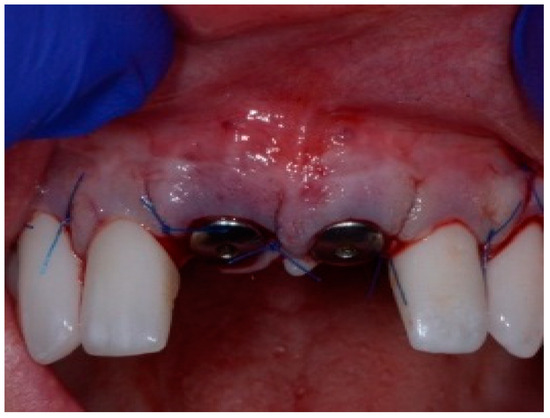

The surgical protocol was followed as described for the previous patient. Likewise, an implant was placed, followed by the placement of bone graft material over the defect and covered with a resorbable membrane. Six months later, the implant was fully intergraded (Figure 10), and the soft tissue appeared to be within normal limits (Figure 11). The implant was restored with a ceramic zirconia crown. Figure 12 presents the patient three years after treatment.

Figure 10.

Radiograph of the lateral incisor.

Figure 11.

Occlusal view of implant site before final restoration.